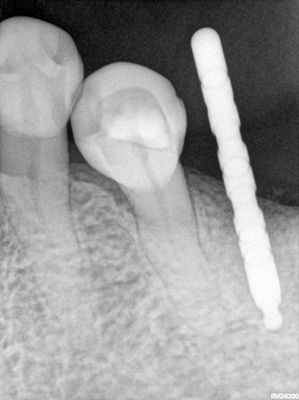

TZeng - 36 and 37

straightforward implant placement.